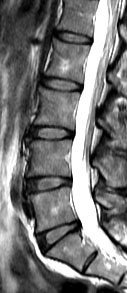

Low back pain affects every population worldwide, and is a leading cause of ill-health and sick leave in the working population of Hong Kong. One of the major causes of low back pain is degeneration of the joints of the spine, known as the intervertebral discs. A cohort study conducted by the Department of Orthopaedics & Traumatology at The University of Hong Kong Li Ka Shing Faculty of Medicine reveals that being obese in adulthood doubles the likelihood of having disc degeneration and developing more severe forms of the condition than those of normal weight. These findings are of public health concern and were published in the latest issue of the authoritative journal Arthritis and Rheumatism.

The current study was a cross-sectional assessment of adults from this cohort who were 21 years of age and older. A total of 2,599 individuals were assessed with magnetic resonance imaging (MRI). Amongst them, 27% (n=709) did not have disc degeneration while 73% (n=1,890) had. Of the subjects who have disc degeneration, 7% were underweight, 48% were in the normal weight range, 36% were overweight, and 9% were obese. Overweight and obese individuals were also found to have a greater extent and severity of disc degeneration in comparison to those individuals of normal weight or underweight.